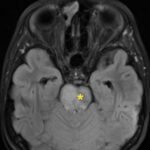

There is a growing body of literature and scientific discovery on pediatric autoimmune encephalitides. This is a heterogenous group of neuroinflammatory conditions leading to often perplexing acute and progressive neurologic and/or neuropsychiatric symptoms. This report demonstrates the evaluation and management of an adolescent with myelin-oligodendrocyte glycoprotein (MOG) antibody-associated fulminant acute disseminated encephalomyelitis (ADEM) in the context of current literature. The featured magnetic resonance imaging uniquely highlights progressive central nervous system lesions detected over the course of the first week of disease.